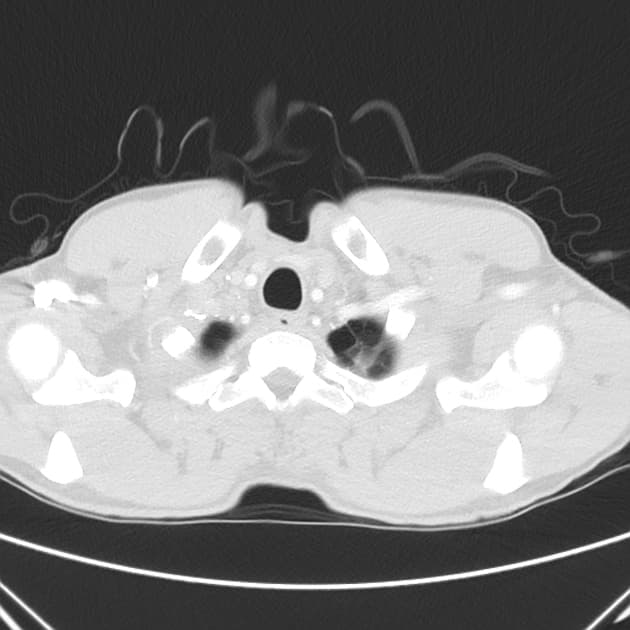

Chụp cộng hưởng từ (MRI) phát hiện tổn thương ở thể gai phải, kích thước khoảng 33 x 27 x 36 mm, ranh giới rõ, kèm theo phù mô não xung quanh lan xuống cuống não phải, chèn ép não thất bên và não thất ba kề liền, đẩy đường giữa sang trái. Trên hình ảnh T2, tổn thương cho thấy dấu hiệu viền kép (double ring sign), tín hiệu thấp trên T1, tín hiệu cao trên T2, và tín hiệu trung gian trên FLAIR. Tổn thương không có tín hiệu thấp trên GRE, có hạn chế khuếch tán (restricted diffusion) rõ rệt ở vùng trung tâm và ngấm thuốc viền (rim enhancement) sau tiêm thuốc cản quang.

1H-MRS cho thấy tổn thương trung tâm có đỉnh lipid, các đỉnh choline, creatine và NAA giảm đáng kể. Vùng ngấm thuốc viền và vùng phù xung quanh tổn thương không cho thấy dấu hiệu xâm lấn của u (không giảm NAA và không tăng choline).

Các hình ảnh trên MRI và 1H-MRS phù hợp với chẩn đoán áp xe thể gai (thalamic abscess). Đây là một vị trí khá hiếm gặp đối với áp xe não.